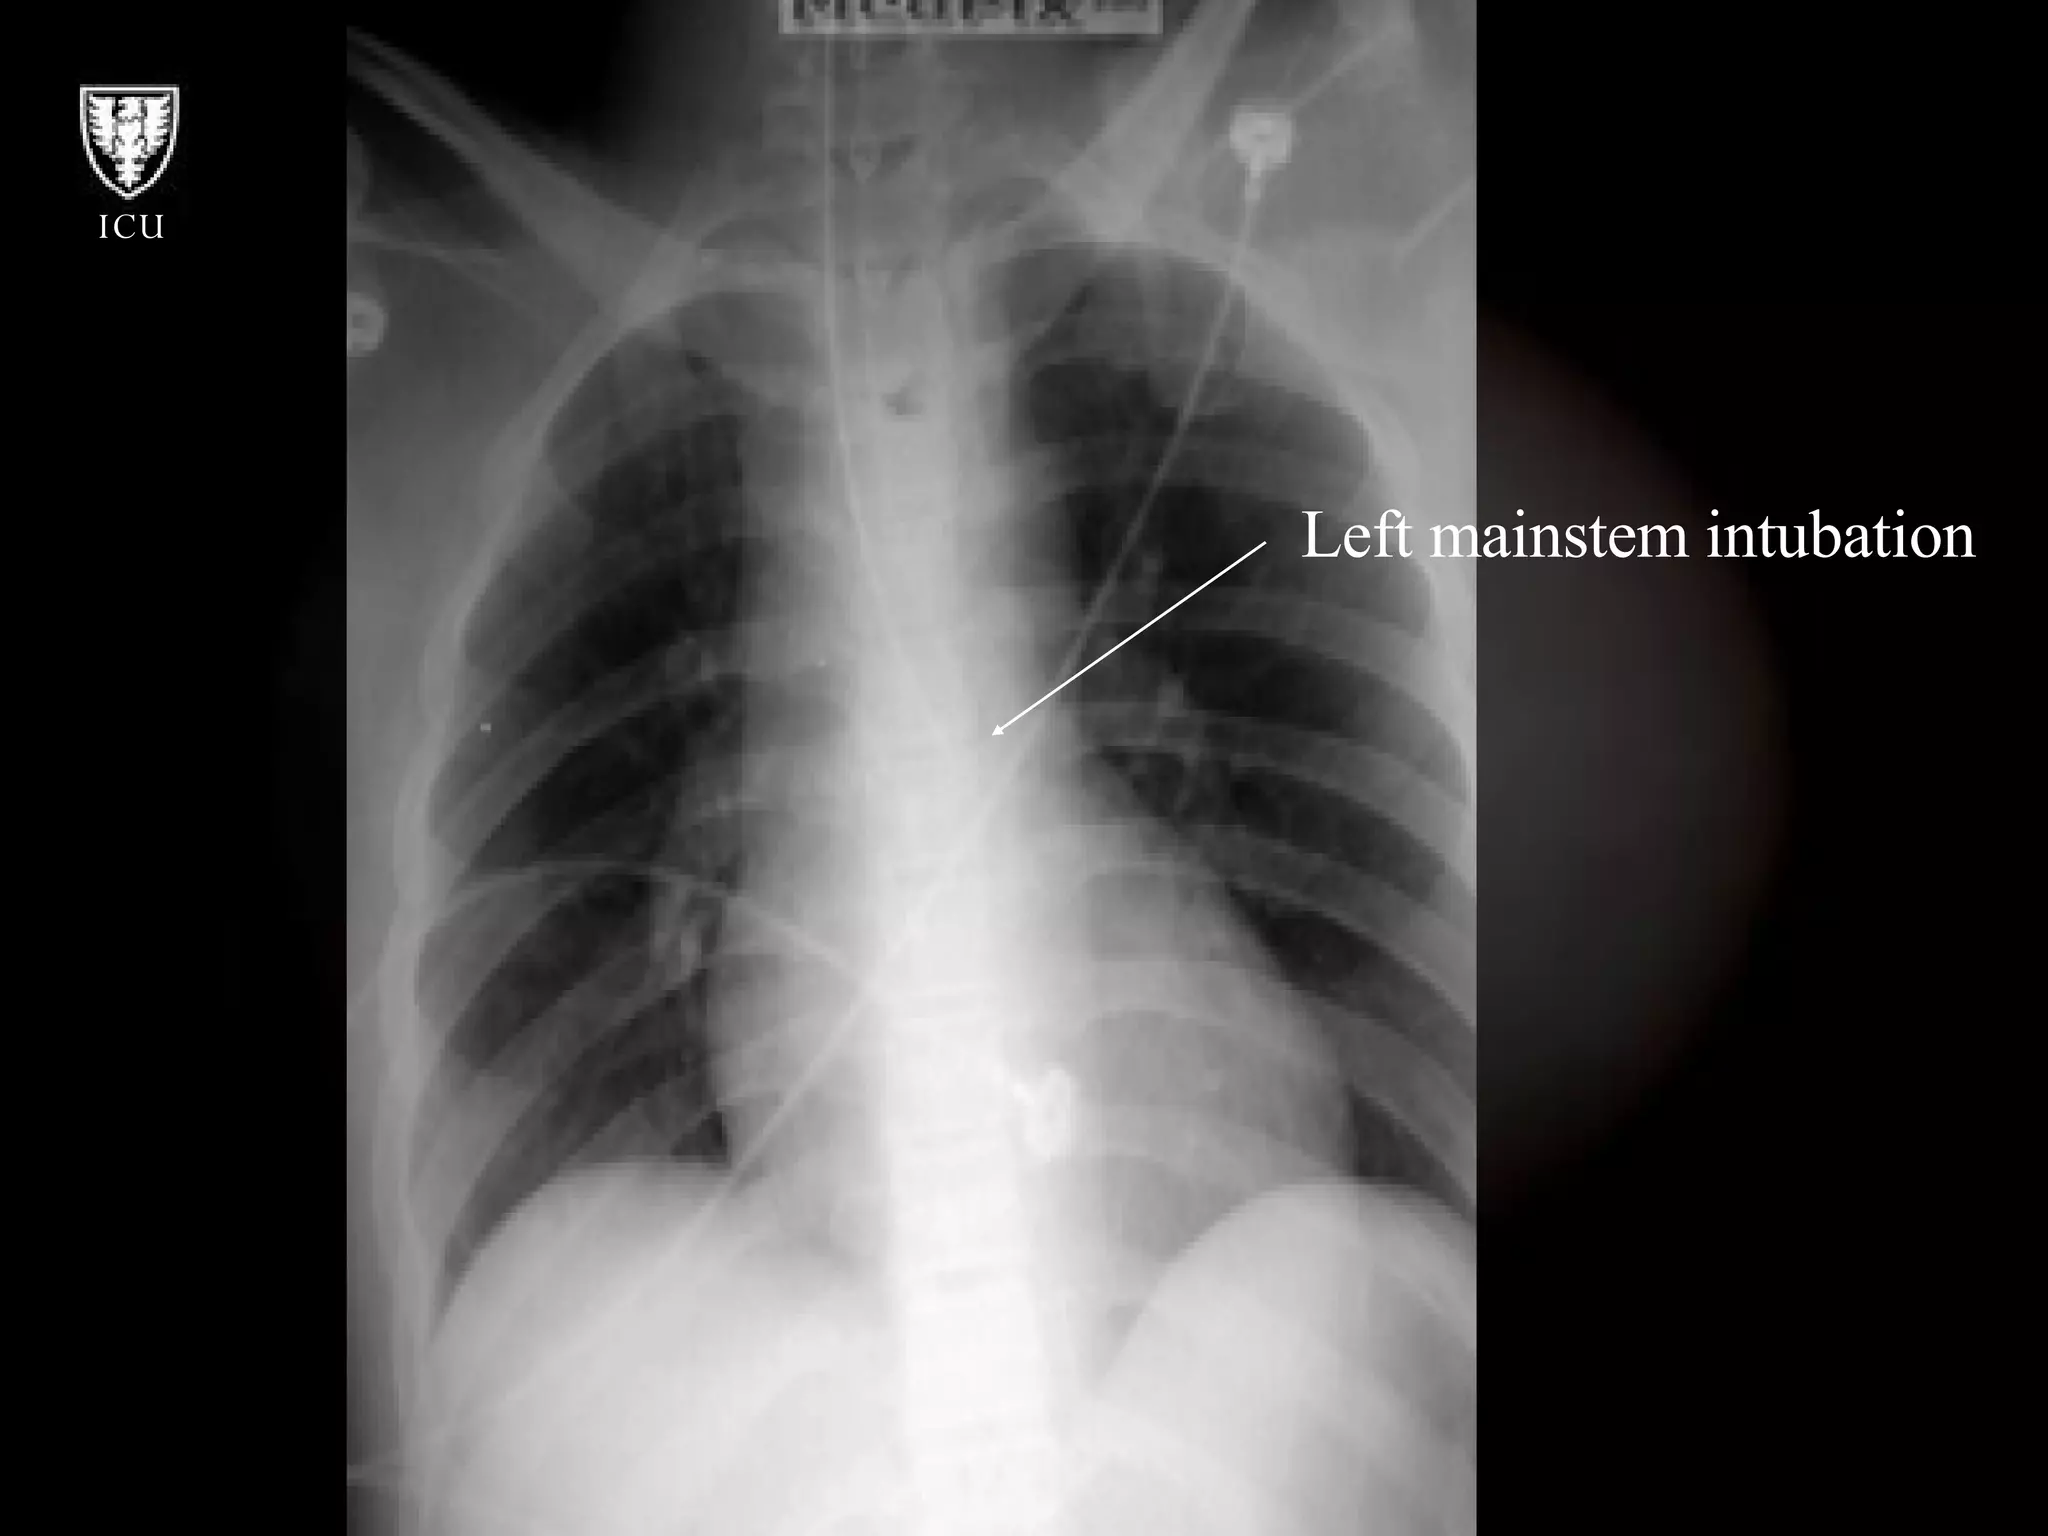

What’s Wrong With These Pictures?

Left mainstem intubation

What’s Wrong WithThese Pictures?